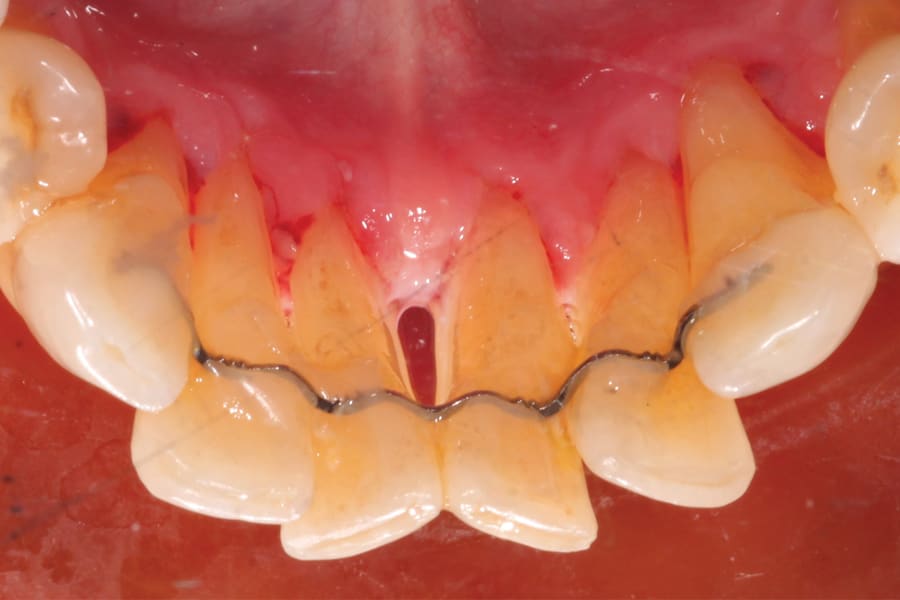

There are, however, some unfavorable long-term ramifications of this design. Due to the nature of stainless steel, which has memory and over time will partially return to its original shape, these twisted lingual retainers may "unwind" or uncoil and exert unintended forces on the teeth to which they are bonded (Figure 5 and Figure 6, Figure 8 through Figure 11, Figure 14 through Figure 16). This leads to excessive labial or lingual root torquing movements, often resulting in highly undesirable recessions, dehiscences, and fenestrations. Because it may take years for this occurrence to manifest, the orthodontist (who usually places the retainer) is typically both unaware of the situation, as he or she does not customarily follow patients for such long-term periods, and free of blame. The periodontal implications of this outcome can be highly detrimental, as seen in the cases presented herein.

Once deformities, such as an undesirable dehiscence or root position, are detected, remedial action should first involve correcting the tooth position. Although this endeavor can take time and be somewhat challenging, it can be accomplished in several ways. First, in all cases, the twisted lingual splint must be removed. Following this, one of three modalities may be used. One is to allow the teeth to relapse. This may not be the most desirable option, as it may also incur other untoward movements, such as allowing the teeth to return to the pretreatment positions. Further, this option will likely be slow to progress.

A second option is to use corrective orthodontic therapy in the form of fixed appliance application to torque the root back into the correct position (Figure 5 through Figure 7). This requires full-sized archwire insertion into a precision edgewise bracket (Figure 7). This can be a time-consuming undertaking, as the step-up through various archwires until fully engaging a full-sized wire will take a few months. Nevertheless, significant corrective changes often can be observed, as the tooth's investing structures often spontaneously remodel, at least partially, in response to the corrected tooth position (Figure 5 and Figure 7, Figure 11 and Figure 13).

A third option for correcting tooth position is via orthodontic aligner therapy (Figure 8 through Figure 13). With this modality, precise 3-dimensional control must be designed and incorporated into the aligner prescription. This option presents a more expedient alternative than the use of conventional fixed appliances, because the aforementioned stepwise progression of increasing the size of archwires is unnecessary, and corrective force can be applied from the onset (Figure 12). Significant overcorrection of the intended movement is recommended in the prescription. In this way, if the aligners do not fully express the movement, continued usage of them may accomplish it. Should the result be attained prior to the conclusion of all aligners, cessation (and more appropriate retention) is indicated.